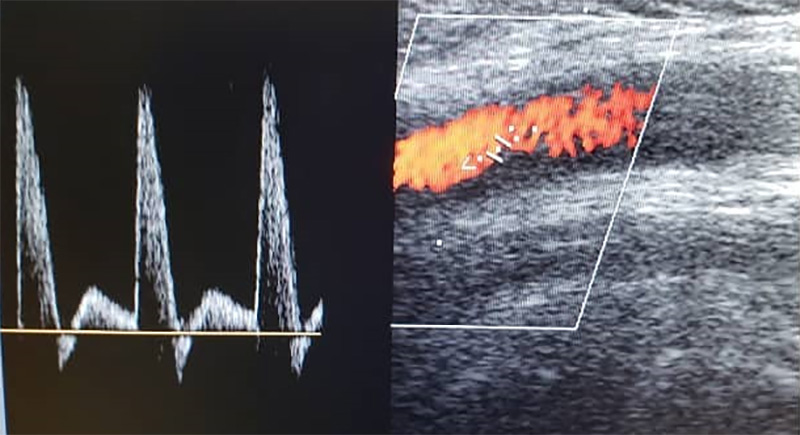

ECODOPPLER

El Eco Doppler es un tipo de ultrasonido que estudia el flujo de sangre que se transporta por las arterias y venas; es decir, permite conocer la cantidad, velocidad y consistencia del flujo sanguíneo en un momento concreto.